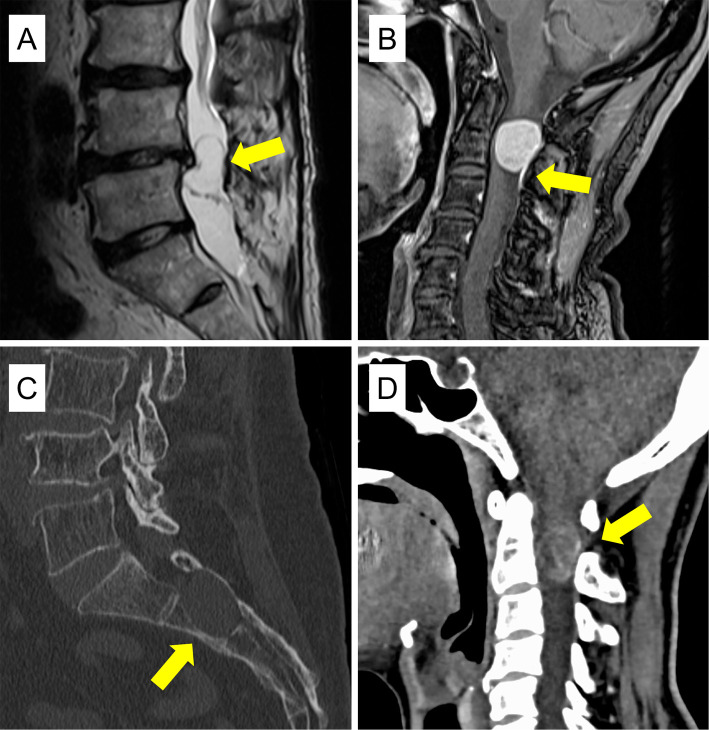

Results: The average age of patients was older (67.6 vs. 58.9 years), and the frequency of females was higher (72% vs. 46%) for meningioma than for schwannoma. Meningiomas were mostly found in the thoracic region (84%), whereas schwannomas were commonly located in the lumbar region (54%). For each tumor type, specific radiological findings were identified. For meningiomas, findings included the ginkgo leaf sign (GLS) (sensitivity 58%, specificity 100%), oval shape (sensitivity 84%, specificity 63%), dural tail sign (DTS) (sensitivity 75%, specificity 100%), and intertumoral calcification (sensitivity 39%, specificity 100%). Combining GLS and DTS greatly improved sensitivity to 89% (specificity 100%). For schwannomas, specific findings included a lobule shape (sensitivity 25%, specificity 95%), dumbbell shape (sensitivity 54%, specificity 100%), and cystic changes (sensitivity 54%, specificity 97%).

Conclusions: GLS may be a specific radiological feature for meningiomas and can aid in diagnosis when combined with DTS. Understanding these distinct radiological characteristics is valuable for preoperative differential diagnosis of intradural-extramedullary spinal tumors.